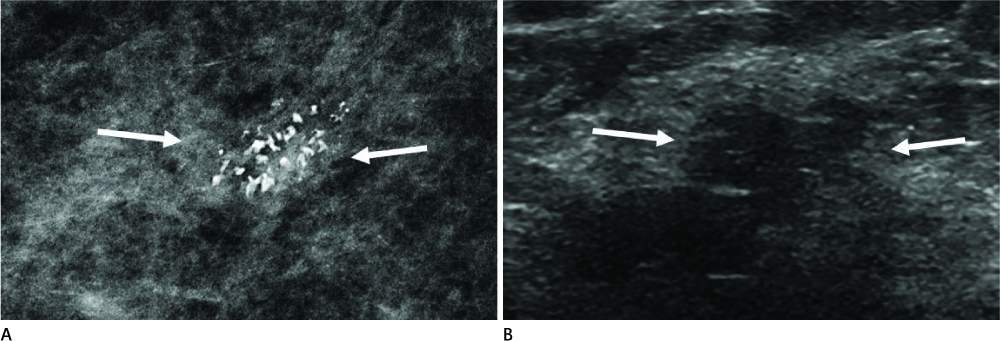

Clinical Significance and Pathologic Outcomes of Coarse Heterogeneous Calcifications Detected on a Mammography

To investigate the clinical significance and pathologic outcome of coarse heterogeneous calcifications (CHCs) detected on a mammography.

A retrospective review of our institutional mammographic database revealed 65 women with CHCs. Of these, we included 27 with pathologic verification (n = 27; benign in 13, malignancy in 14). Mammograms were interpreted in terms of CHC distribution (clustered, linear, segmental, regional, or diffuse), the area of CHCs, and associated findings. We also evaluated the presence of mass, ductal change, or change of parenchymal echogenicity on ultrasound images (n = 26). We correlated and statistically analyzed the radiologic features with pathologic findings.

The individual distributional descriptors of CHCs predicted the risk of malignancy as follows: clustered (8/22); linear (1/2); regional (0/1); segmental (5/5). The segmental distribution predicted malignancy (p < 0.05). The CHC area in malignant lesions was larger than that of benign lesions (p < 0.05). Mammography revealed an associated mass in 2 out of 13 benign and 5 out of 14 malignancies. However, an increased risk of malignancy was not shown by the presence of an associated mass and its larger size. Ultrasound findings were not significant for predicting malignancy.

CHCs were verified as malignancy in 52% of cases, especially when characterized by segmental distribution and larger CHC areas on mammography.